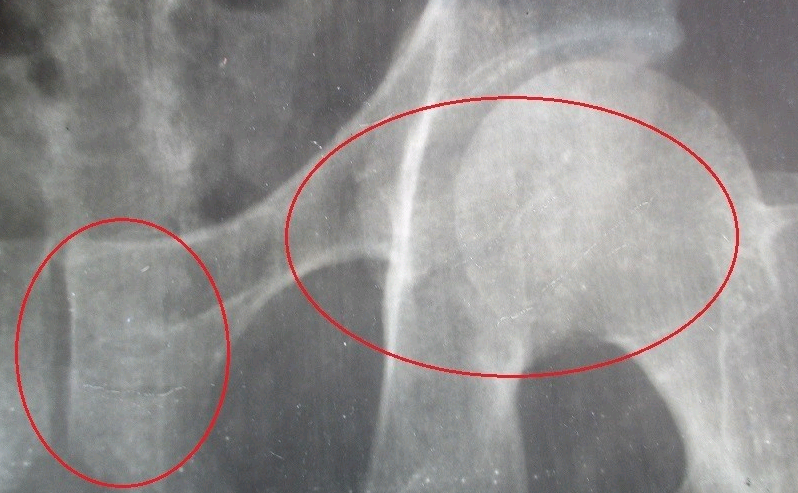

我在2008年4月因为工作原因导致盆骨骨折不能走路,惠州市相关劳动部门不作为,因此只好自费到广东省惠州市平

潭镇人民医院检查。

由于惠州市相关卫生行政监管不力等原因,造成平潭人民医院,在没有医疗条件和专业人员的情况下,没有经过任何

批准和手术条件:非法开设“腰牵引”手术,并且以传销形式拼命发展他人去做“腰牵引”手术,以此长期非法手术牟取

暴利,并且因此造成数额巨大的众多无辜者被手术形成残废(腰牵引手术只要一旦做了,就会造成不同程度的残废;

严重的断脊柱、骨架散,肩膀掉到腰位置都有;法人代表院长严佩荣后来升职到惠阳区疾病防控中心做副主任;涉案

其他一些人都升职了;···);我是事件揭发举报人、也是受害者,本来纯属是盆骨折、腰椎正常的,但无牌无证没有

培训过的x光检查室主任香某光,违规操作x光机检查不骨折情况下、当然不肯放弃我这个送上门的“病人”,因此他开

了所谓疾病证明把我叫去做“腰牵引”手术。

骨科兼“腰牵引”手术的主任医生朱某友,没有履行责任查看骨片的责任、

也没有说明“腰牵引”手术的危害,就也把我安排去做“腰牵引”手术,和其他无辜“病人”一样由他没有培训过的老婆和

隔壁闲着的性病科医生以及社会人员对我进行手术。

手术做了一个多月,造成:原来的盆骨骨折更加严重,另外:没有任何问题的躯主骨架,被手术床拉散架了,大面积

肋骨异位变形、腰椎、脊柱变形、腰关节等等骨折老化腰骨爆裂、脖子到肩胛骨周围的肋骨胸骨也异位松动,因此连

起床也困难、支撑两个手的骨架松脱了因此两手麻木、举手投足受到相当限制异常痛苦···我一身好好的主骨架被“肢

解”报废。

惠州市卫计局、惠州市中心医院局于利益或者政治压力也显然助纣为虐,另外:医疗伤害不公开这个应该是潜规则,

因为CT骨片显示我骨架散架···可去鉴定反而被进一步伤害,惠州市和广东省的两级医学鉴定都进行鉴定,他们都和卫

生行政一样,睁着眼睛说瞎话包庇了这些罪恶、因此形成腐败串案:把出事医院责任推脱得一干二净!导致无法维

权,因此对于我生存生活与家庭无疑是灭顶之灾!

现在:我个人因为平潭医院的非法手术,造成主骨架散架、整条脊柱变形关节老化、腰骨折、大量肋骨异位、支撑双

手的肩胛骨和胸骨也异位······连呼吸都难受呀!另外:在广州市萝岗看守所、北京西城区看守所和惠州市惠阳区看守

所,被虐待殴打分别造成的耳朵残废、气管破裂不愈合···虐待造成的视力障碍等等伤残、以及胸部软骨骨折恶化。·还